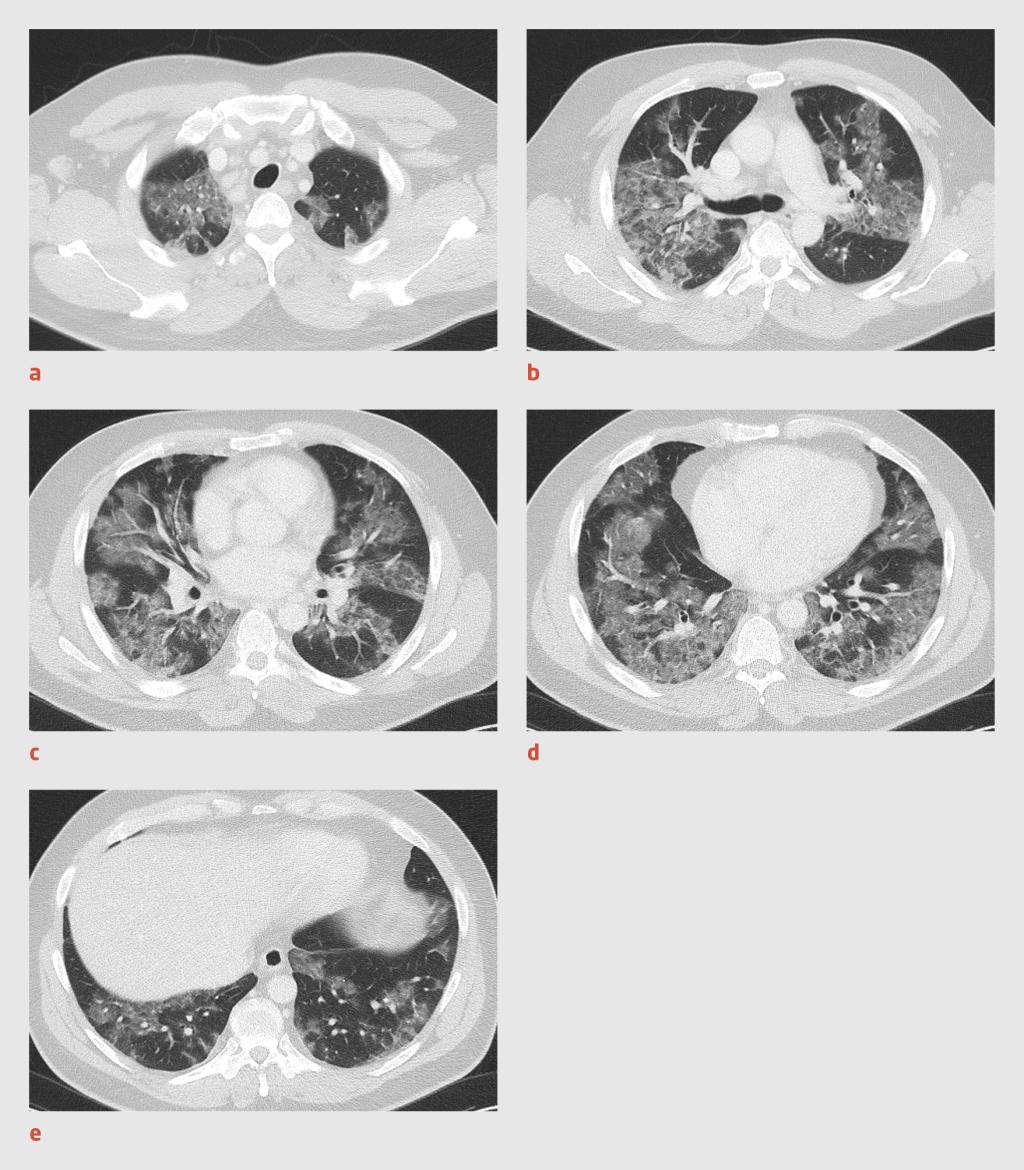

Bij de 12 patiënten die tot en met 13 maart werden opgenomen op de IC was 75% van de thoraxfoto’s bij opname afwijkend. Bij 4 patiënten, die uiteindelijk allemaal in de periode tot en met 13 maart op de IC werden opgenomen, werd bij opname een CT van de thorax verricht. Bij 1 patiënt werd de thoraxfoto niet-afwijkend afgegeven en toonde de CT-scan wel een consolidatie. Voor de overige 3 CT-scans was de bevinding conform de thoraxfoto, waarbij de meest kenmerkende bevindingen diffuus verspreide peribronchiale centrale en perifere matglas afwijkingen waren (figuur 2). Daarnaast was er bij 1 van de CT-scans sprake van minimale mediastinale lymfadenopathie.

Figuur 2

Afwijkingen op CT-scan bij COVID-19

Figuur 2 | Afwijkingen op CT-scan bij COVID-19

CT-scans van 1 van de 29 eerste patiënten met COVID-19 uit een ziekenhuis in Noord-Brabant met diffuus verspreide peribronchiale centrale en perifere matglas afwijkingen.